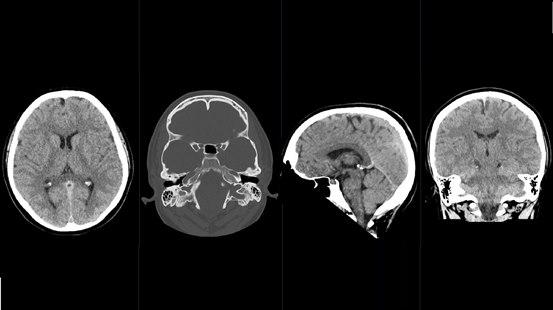

CT av hjernen betegnes på fagspråket for cerebral CT. Bildene som tas brukes til å fremstille hjernevev, hinner og blodårer inne i hodet. Bløtvev med ulik tetthet kan skilles fra hverandre, og i hjernen kan f. eks. hjernebark og hjernemarg (grå og hvit substans) skilles fra ryggmargsvæsken. CT er godt egnet til å vise f.eks. akutte blødninger i hjernen, men når man skal vurdere hjernevev er MR en langt mer detaljert undersøkelse.

Bildene vises i ulike gråtoner. Jo lysere skygge, jo høyere tetthet har vevet eller strukturen. Bein blir hvitt, mens luft blir svart. Tilførsel av røntgenkontrast via blodet kan gi bedre bildeinformasjon, f.eks lar store blodårer seg lettere fremstille etter tilførsel av kontrast i årene.